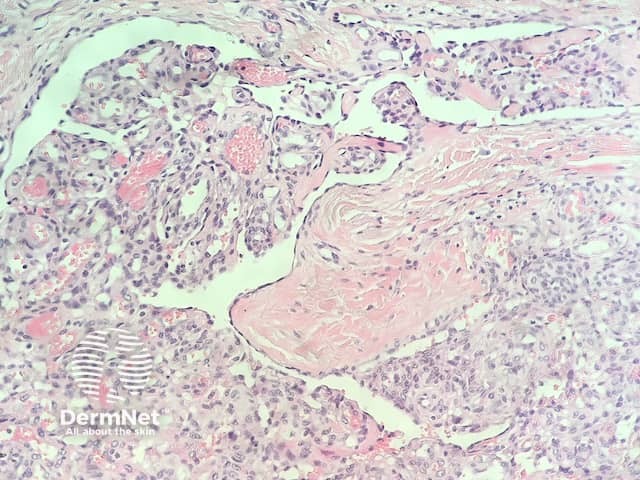

In glomeruloid haemangioma, the histopathology shows numerous dermal ectatic vascular spaces lined by flat endothelial cells. Inside these dilated vascular spaces are a conglomeration of capillaries lined by plump, swollen endothelial cells, filled with red blood cells, resembling renal glomeruli (figures 1–4).